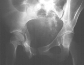

Radiographs:

Radiographs revealed a vertical buckle fracture of the right inferior sacrum, oblique fractures of the superior and inferior rami on the right and a fracture through the medial acetabulum. Obturator and iliac oblique inlet and outlet pelvic views, and a thin cut CT with 3-D reconstruction of the acetabulum were performed. These elucidated a comminuted anterior wall with fracture line extending to the posterior column. The posterior column was non-displaced. The pelvic fracture was non-displaced.

1. Right T-shaped acetabular fracture with anterior wall comminution.